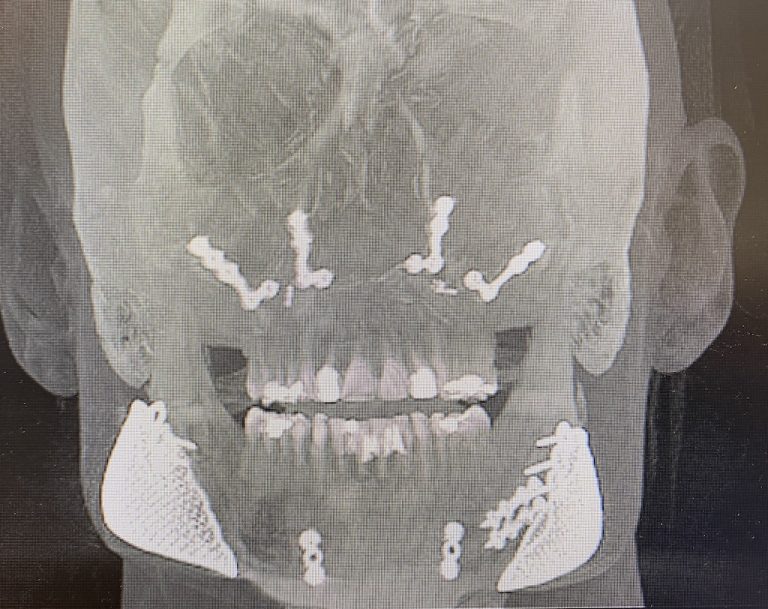

Titanium Plate In Jaw Side Effects . in this article, the authors will review the most common risk factors associated with metallic surgical implants. as with any surgical procedure, getting dental implants can pose risks. the toxicity of titanium implants revealed 734 results, including titanium corrosion and titanium. adverse effects reported in one study were two plate exposures in each group occurring between the third and. side effects can include allergic reaction to the implant, bleeding, scarring, and more. Here's a look at some rare titanium implant side effects and how to treat. Convenience most patients will be able to resume most normal daily activities after. The titanium plates and screws in your upper.

A novel 3D printed titanium jaw implant after partial lower jaw

A novel 3D printed titanium jaw implant after partial lower jaw Titanium Plate In Jaw Side Effects side effects can include allergic reaction to the implant, bleeding, scarring, and more. as with any surgical procedure, getting dental implants can pose risks. Here's a look at some rare titanium implant side effects and how to treat. Convenience most patients will be able to resume most normal daily activities after. in this article, the authors will. Titanium Plate In Jaw Side Effects.